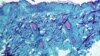

Variola maimuţei se transmite prin contact fizic strâns. Simptomele includ febră, erupţii cutanate extinse, leziuni ale pielii şi ganglioni limfatici umflaţi, după o perioadă de incubaţie de cinci până la 21 de zile.